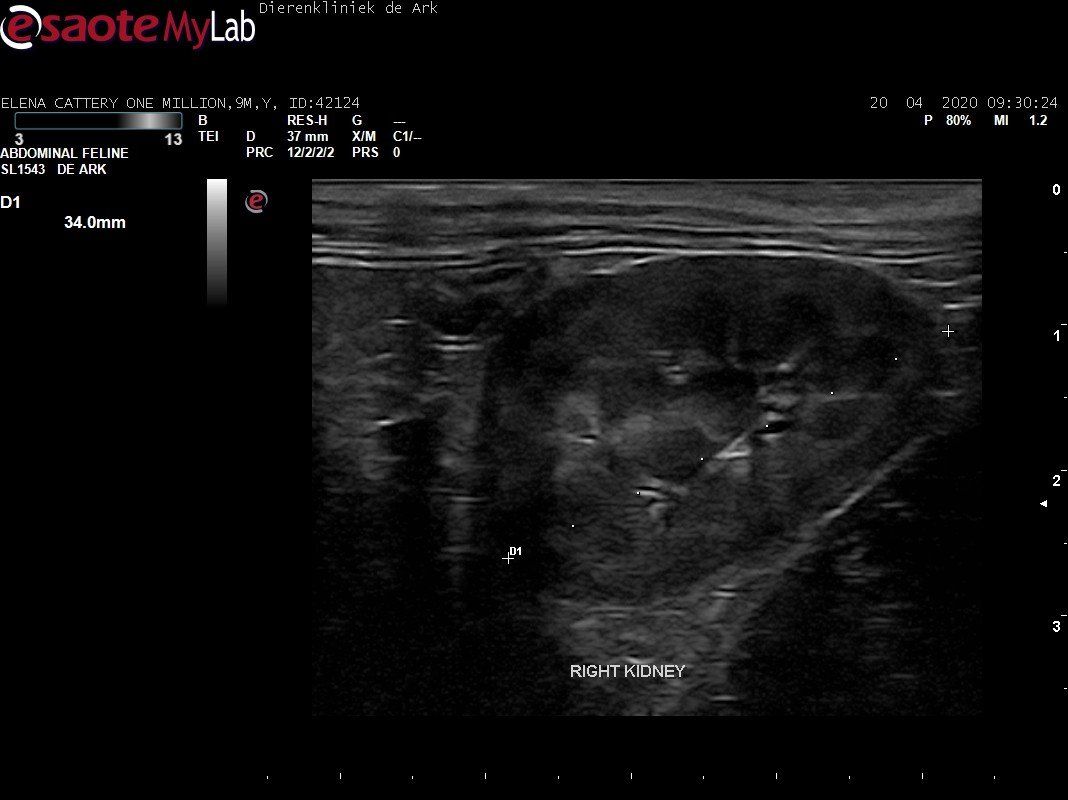

3,200 kg , echo en nieuw bloedonderzoek gedaan wat perfect ging door middel van gapabetine

Voor de garanties en om recht te hebben op medicatie bij herval eist Mutian diverse onderzoeken en controle momenten. Dit zijn bloedonderzoeken maar ook zoals hieronder te zien is echo's. Elana is volledig gecontroleerd op afwijkingen, gelukkig waren de echo's goed.

Ook de bloeduitslagen waren in orde, we kregen groen licht om te stoppen met behandelen en de wachtperiode in te gaan.